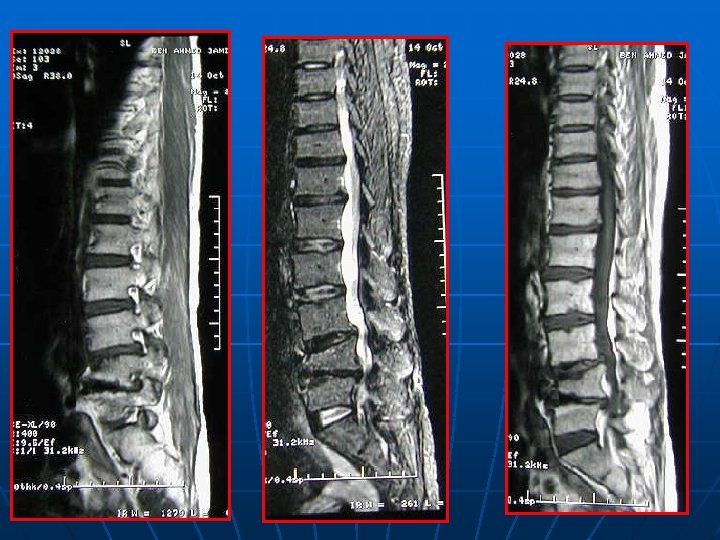

IRM n n EXAMEN CLE INCONVENIENTS : * statique * scoliose plan de coupe différent pour les étages STENOSE : centrale, foraminale ou associée (intérêt des coupes latérales foraminales) STRATEGIE OPERATOIRE+++ : ° état des disques (Modic? ) ° direction interligne articulaire : déstabilisation postopératoire?